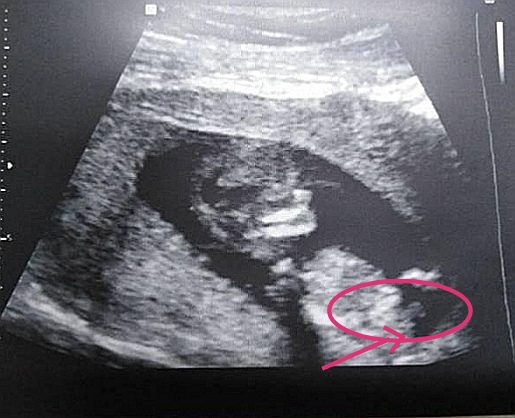

Вот внизу торчит, смотрите 11 недель вот такой наклон